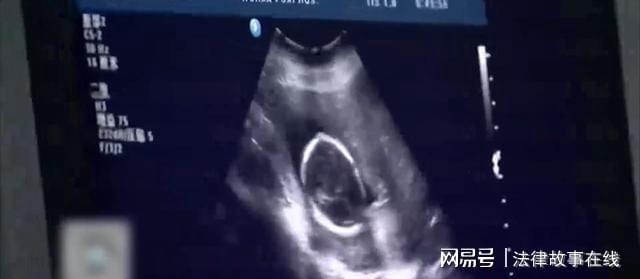

并非她们不愿意为弟弟捐献骨髓,也并非她们没有配对成功,而是配对成功的人竟然只有柯旭的二姐一个人。想到医生之前说的话,又看到柯希的稍微隆起的腹部,大姐和三妹都和柯希一起陷入了沉默。

要知道之前柯希拿家里的钱为弟弟缴纳费用时,几乎掏空了家底,如今又要将腹中的双胞胎引产,实在有些不好意思和丈夫开口。不过为了帮助患病的弟弟,柯希还是毅然作出了自己的抉择,同时也把这件事告诉了丈夫。